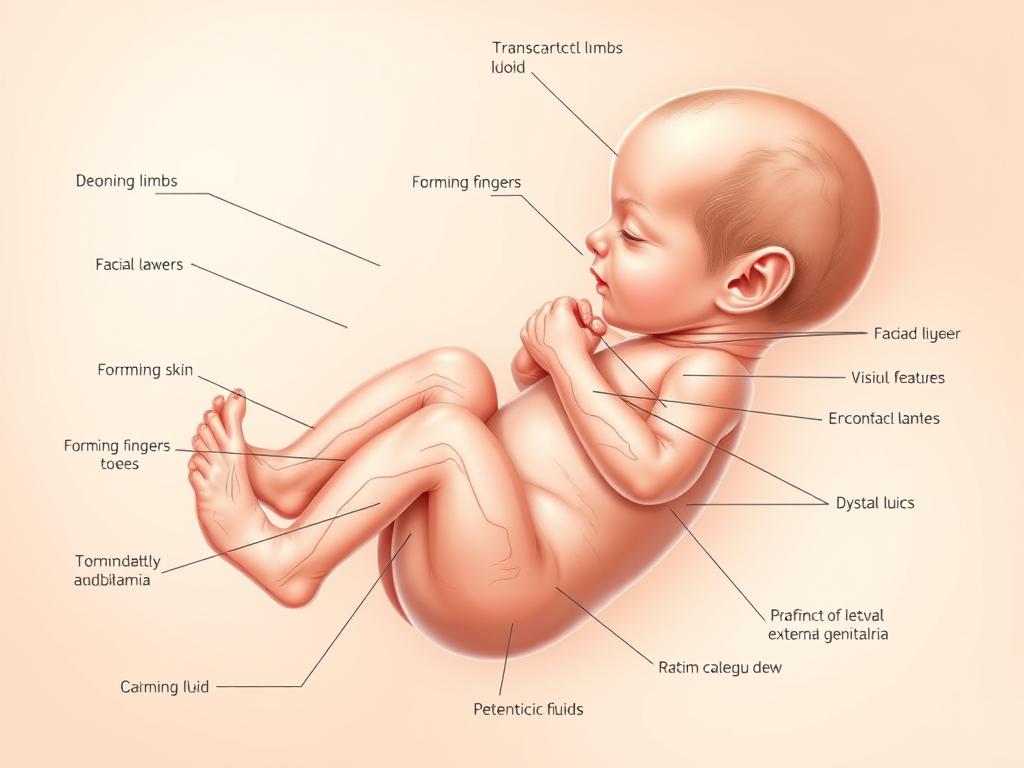

Wizualizacja płodu w 12 tygodniu ciąży – widoczne kształtujące się kończyny i rysy twarzy

W 12 tygodniu ciąży Twoje dziecko przechodzi fascynujący etap rozwoju. Płód mierzy już około 5-6 centymetrów długości (od czubka głowy do pośladków) i waży około 14-16 gramów. Jego wielkość można porównać do dużej śliwki lub limonki [2]. To już nie jest mały zarodek – Twoje dziecko coraz bardziej przypomina miniaturowego człowieka.

Wszystkie najważniejsze narządy wewnętrzne są już uformowane i zaczynają funkcjonować. Serce bije regularnie, a układ krwionośny sprawnie transportuje krew po całym ciele. Nerki zaczynają produkować mocz, który jest wydalany do płynu owodniowego. Wątroba i trzustka również podejmują swoje funkcje, a jelita przesuwają się z pępowiny do jamy brzusznej [3].

Twarz dziecka w 12 tygodniu ciąży – widoczne kształtujące się oczy, nos i usta

Twarz Twojego dziecka nabiera coraz bardziej ludzkich rysów. Oczy, które wcześniej były umieszczone po bokach głowy, przesunęły się do przodu. Powieki są już uformowane, ale pozostają zamknięte i zrośnięte – otworzą się dopiero około 24 tygodnia ciąży. Nos, usta i uszy również przyjmują swój właściwy kształt i położenie [4].

Na tym etapie ciąży rozwijają się również paznokcie u rąk i stóp, a na głowie pojawiają się zawiązki mieszków włosowych. Skóra dziecka jest jeszcze bardzo cienka i przezroczysta, przez co widoczne są naczynia krwionośne. Stopniowo zaczyna przybierać różowawy odcień [2].